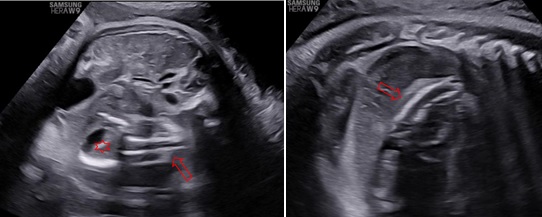

Siêu âm ngã bụng với máy HERA W9 (Samsung) ở các thời điểm 31 tuần 4 ngày, 34 tuần 3 ngày và 39 tuần. Ở hạ sườn trái và cực trên của thận trái có một khối không đồng nhất với kích thước tăng theo tuổi thai lần lượt là: 45x50x42mm, 48x58x50mm và 80x74x66mm. Bên trong khối này thấy hình ảnh vôi hoá có dạng của xương vòm sọ, xương đùi, xương sống và hình ảnh các cấu trúc này rõ khi tuổi thai lớn hơn. Trên Doppler màu, có một mạch máu nuôi khối này xuất phát từ động mạch chủ bụng của thai vật chủ với dạng sóng của động mạch rốn.

Hình 3: Thai 39 tuần, mặt cắt ngang và dọc bụng, cho thấy trong khối này có các cấu trúc giống vòm sọ (dấu sao) và cột sống (mũi tên) được quan sát rõ hơn.